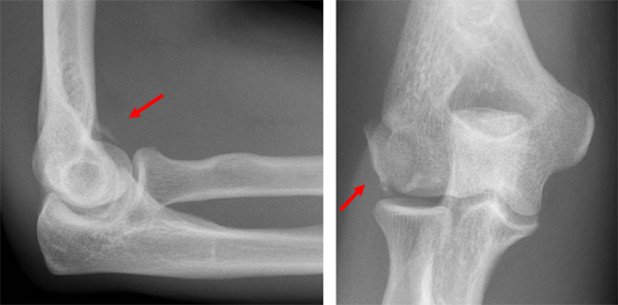

Frakturen am Ellenbogengelenk gehören auch in 2 Ebenen abgeklärt. Eine Röntgenaufnahme in der ap- und seitlichen Projektion sind zu fordern. Hiermit lassen sich die häufigsten Frakturen darstellen. Radiuskopffrakturen, Olecranon-Frakturen und distale Humerusfrakturen.

Wie an diesem Beispiel (Abb. 8) dargestellt zeigt sich eine mehrfragmentäre Radiuskopf-Fraktur, welche letztendlich zur Resektion des Radiuskopfes führte, da sie nicht rekonstruierbar war. Die intraoperative Darstellung zeigt die mehrfragmentäre Radiuskopffraktur.